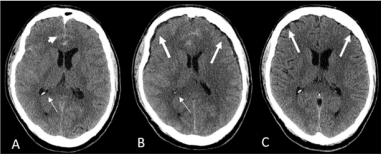

A 57-year-old male presented with a Hunt and Hess grade 2 and Fischer grade 3 subarachnoid hemorrhage (SAH) (Figure 1).

Figure 1 Axial non contrast head CT shows (A) subarachnoid hemorrhage (short arrow) without ventriculomegaly (thin arrow). (B) Bi-frontal extra axial fluid collections or external hydrocephalus (thick arrows) without ventriculomegaly (thin arrow). (C) Resolved extra axial collections (thickarrows) and subarachnoid hemorrhage.

Coil embolization of a 6 mm anterior communicating artery aneurysm was performed without incident. Two days post ictus, the patient complained of a worsening headache with no accompanying neurologic deficit. A non-contrast head CT demonstrated CSF attenuating prominence of the bilateral frontal extra axial spaces without associated mass effect or ventriculomegaly. The patient’s pain was managed with opiates and he was closely monitored in the intensive care unit. He remained hemodynamically stable with no neurologic change. A head CT obtained on day 7 post ictus revealed complete resolution of the extra axial fluid collections and SAH. The patient was discharged on day 14, with resolution of his headache and without a neurologic deficit.